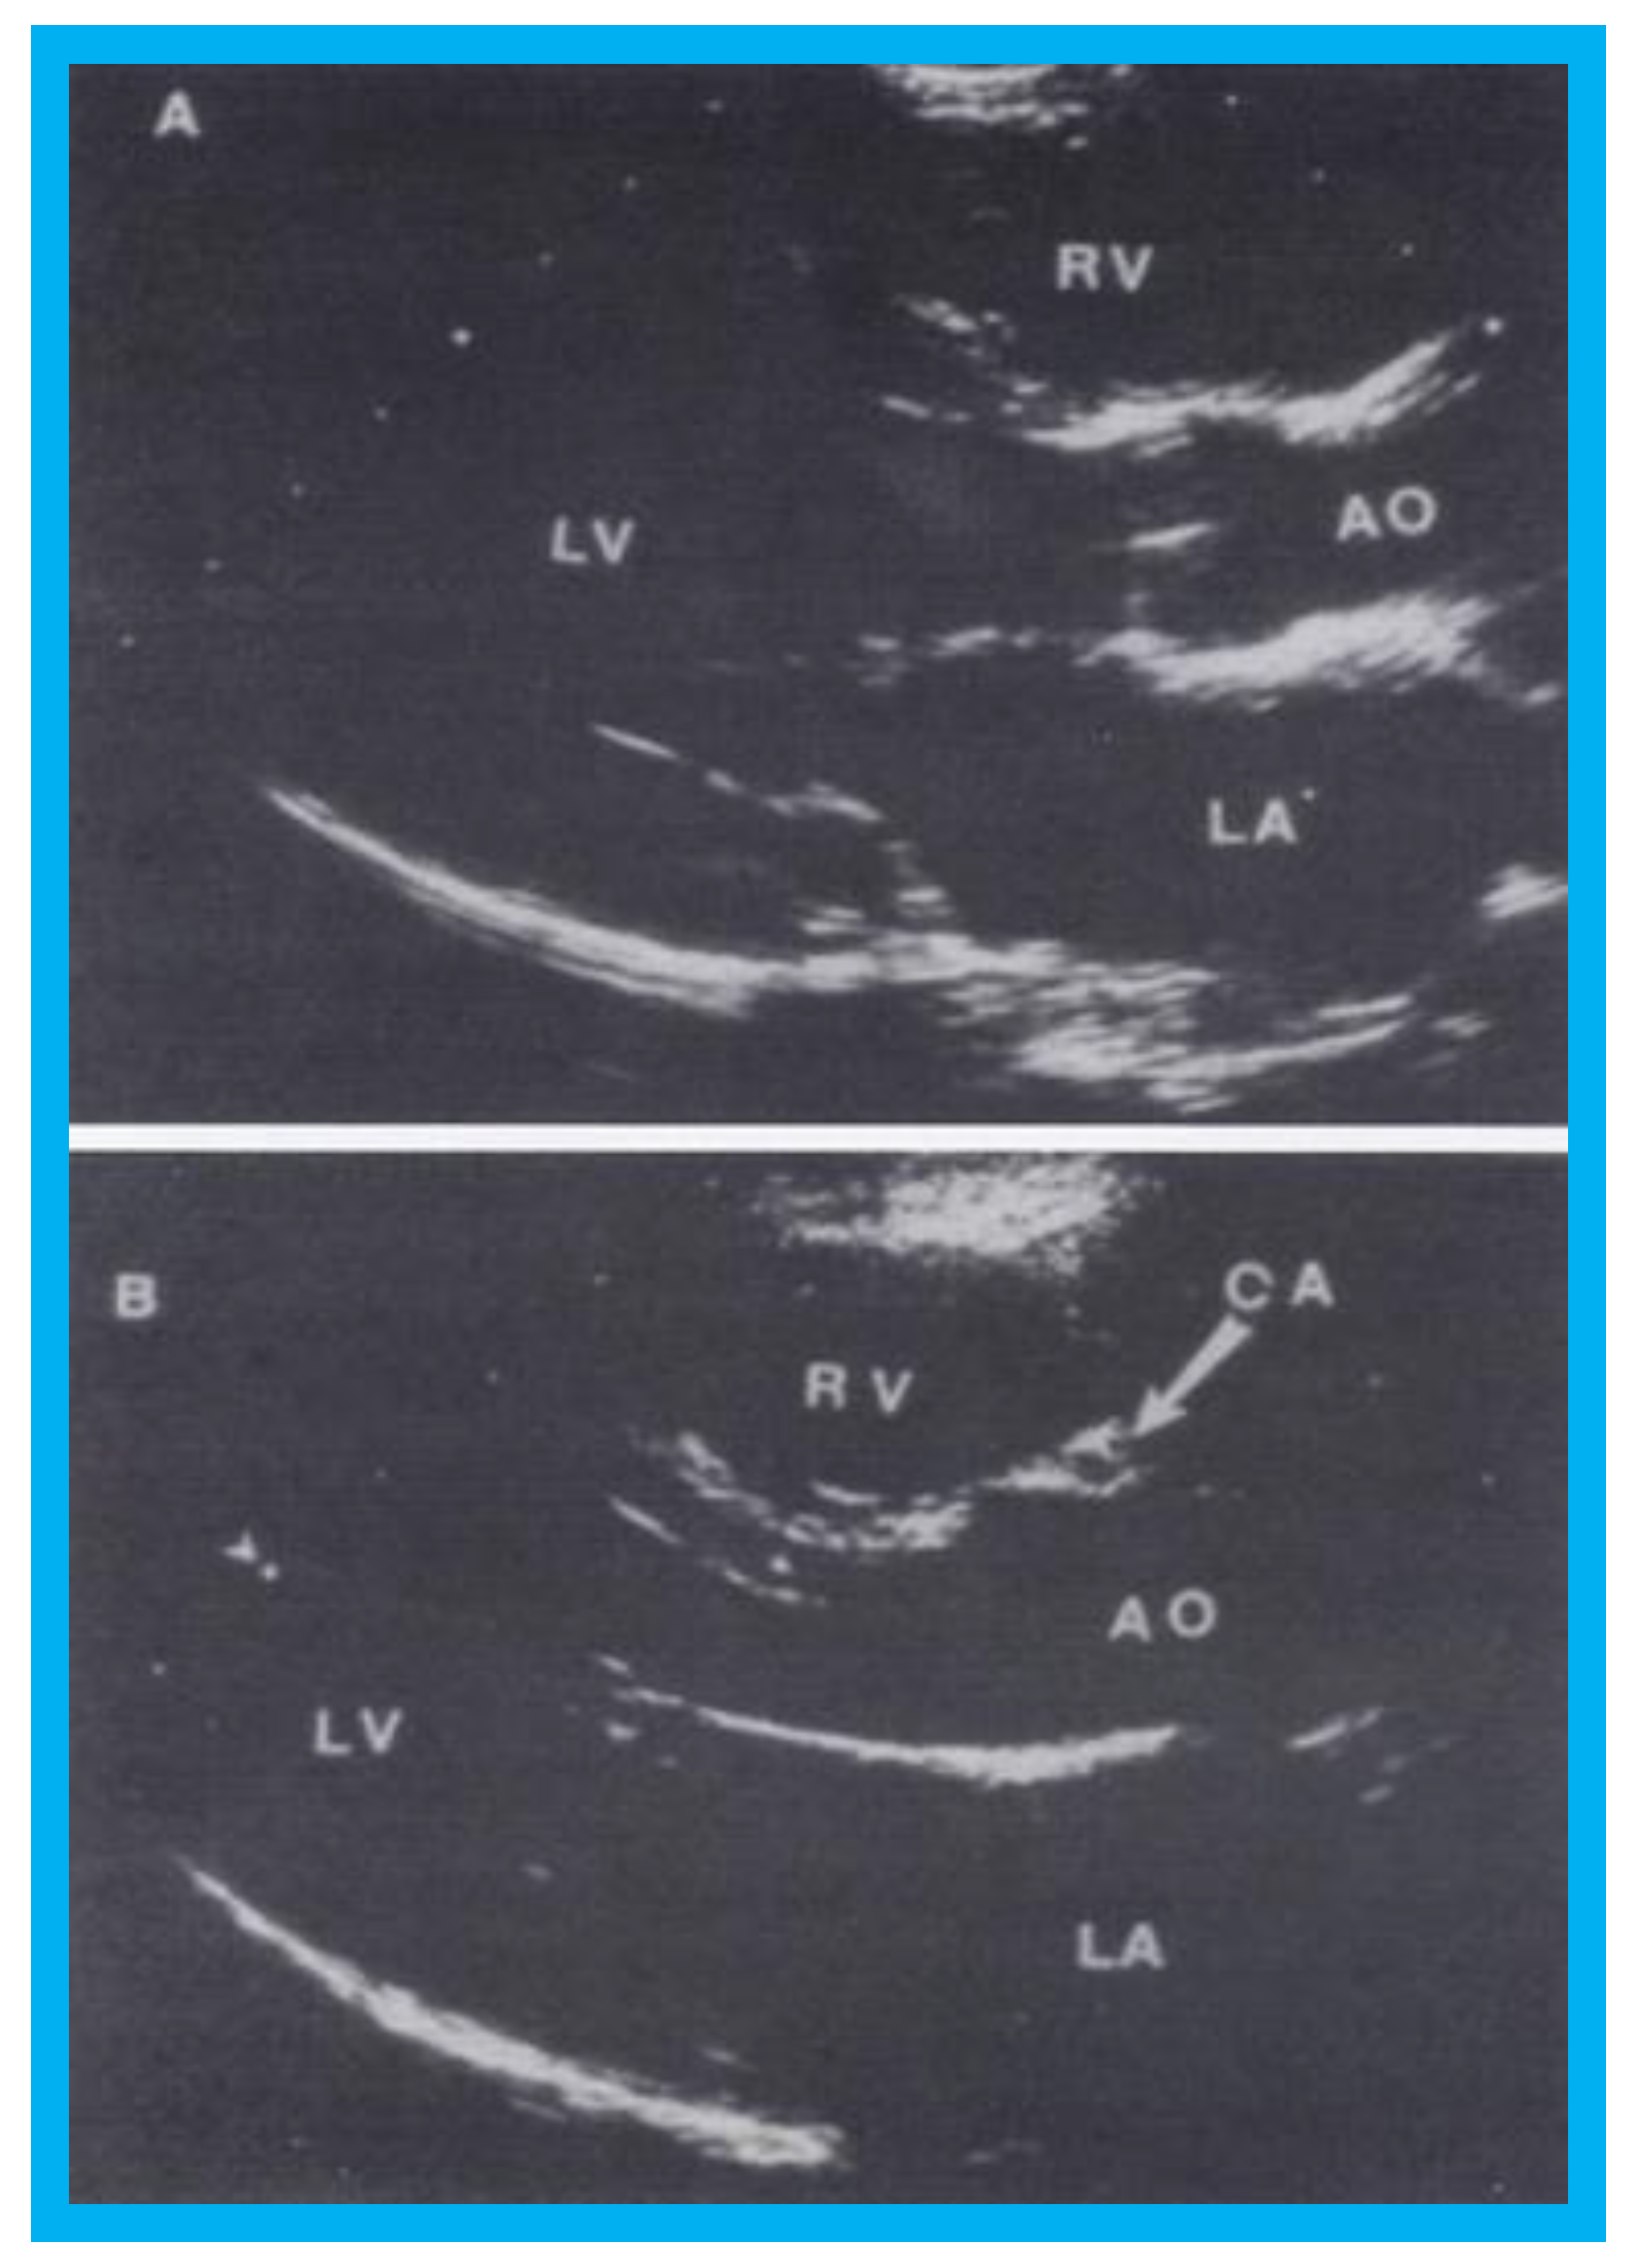

The first of these studies concluded that absent or small left innominate vein (less than 47% of the size of the innominate artery) predicts the existence of a persistent left superior vena cava [13]. The second study demonstrated that coronary artery flow velocity patterns can be recorded and quantified in the majority of children and that the level of left coronary artery flow velocity increases in proportion to the degree of left ventricular hypertrophy [14]. The third study demonstrated that presence of a coronary arterial cross-sectional image in the anterior wall of the aorta in the long-axis view of the LV/aorta (Figure 12) is a useful screening tool to detect aberrant coronary artery in children [15]. Additional details of these studies can be found in the respective publications [13,14,15] for the interested reader.

Figure 12. Selected video frames from parasternal long-axis view in a normal child (A) and in a child with aberrant coronary artery (B): Note a cross-sectional image of the coronary artery (CA) is seen in (B) in the anterior wall of the aorta (AO) while such is not seen in (A). LA, left atrium; LV, left ventricle; RV, right ventricle. Reproduced from Jureidini S.B., et al. [15].